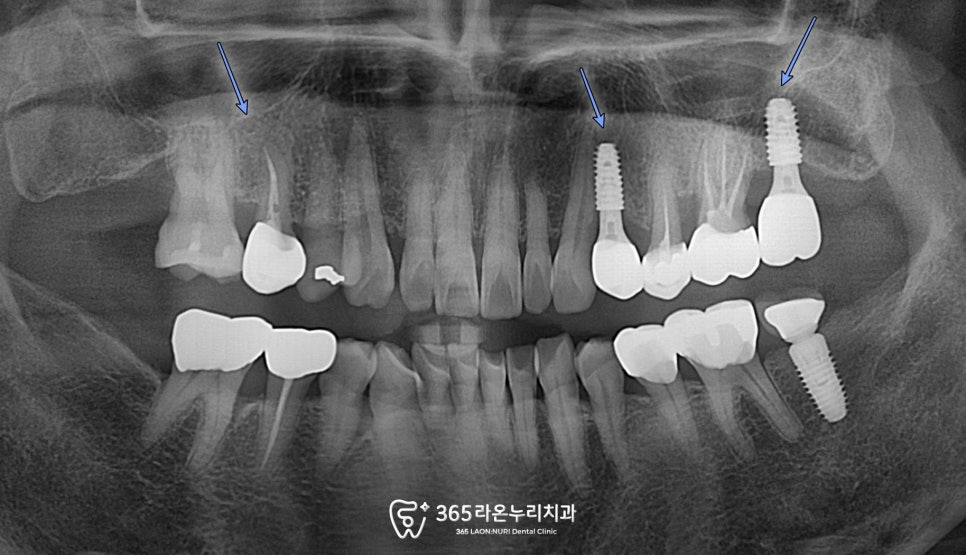

▮ 초진

먼저 오산대역 치과 에서

문제가 있는 치아들을 보겠습니다.

뿐만 아니라 비어있는 치아,

우식증이 심한 치아와

크랙이 있는 치아 등

문제점을 차근차근 해결하는

과정이 필요해 보입니다.

위 사진을 보면, 얼마나 충치가 깊게

파고 들어가 있는지를 보실 수 있습니다.

이렇게, 남아있는 치아들이 멀쩡하지 않길

때문에 환자께서는 일상생활에서 여러 가지

제약이 있을 수밖에 없는 상황입니다.

저작 기능 결손 및 여러 가지 문제에 직면을

하셨기 때문에 임플란트 시술로 대체를 해드리지

않는 이상에는 상황이 더 개선될 여지는 없습니다.

아울러, 그나마 남아있는 치아들로 저작활동을

이어가려 했을 땐 그 남아있는 치아들 마저도

수명이 단축될 수밖에 없으며

심지어는, 턱관절 문제가 나타날 수 있는

좋지 않은 상황이었습니다.